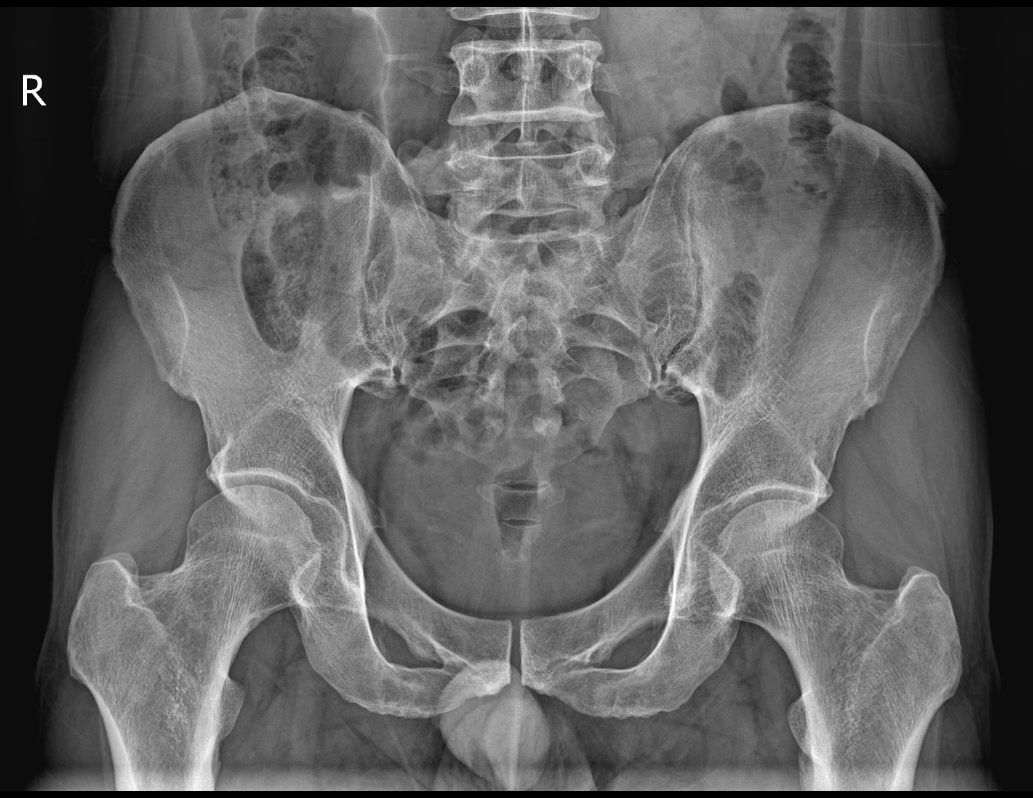

接诊的肛肠科主任医师宋网筛以其敏锐的洞察力和丰富的临床经验,迅速察觉到了问题的严重性。他深知,肠道异物若不及时处理,极有可能引发严重的并发症。当即为程先生安排了CT检查,以明确异物在体内的具体位置及大小形态。检查结果显示,直肠及乙状结肠交界处可见异物影,前端另见棒状金属影——这正是那把“误入歧途”的电动牙刷。面对这一特殊情况,宋主任果断建议程先生立即住院接受治疗,取出异物,以免延误病情。

手术过程中,肛肠科团队小心翼翼地插镜至直乙交界,终于发现了那把“躲藏”在肠道内的电动牙刷。由于电动牙刷体积较大且形状不规则,取出过程困难。大家默契配合,使用异物钳联合圈套器牵引圈住异物尾端,然后逐渐向肛侧牵引。在患者的配合下,经过尝试和调整,最终顺利将电动牙刷取出。

术前

095538tkbddzpd8tozhwjd.png

术后